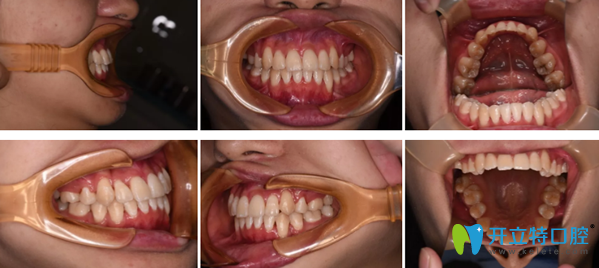

兩年過去了,我來拆了金屬牙套,看看北京拜博口腔正畸效果怎么樣?

鄭州拜博口腔正畸效果案例

現(xiàn)在,我的牙齒很整齊,也很健康。以前外突的虎牙、齙牙、牙齒擁擠錯(cuò)亂等問題統(tǒng)統(tǒng)不見了。整個(gè)人也自信陽光了!